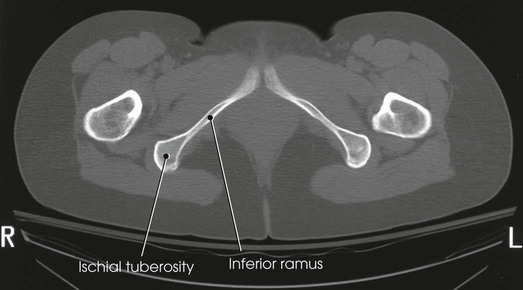

The ischium consists of a body and the ischial ramus. The body of the ischium forms approximately two fifths of the acetabulum posteriorly (see Figs. 7-2 and 7-3). It projects posteriorly and inferiorly from the acetabulum to form an expanded portion called the ischial tuberosity. When the body is in a seated-upright position, its weight rests on the two ischial tuberosities. The ischial ramus projects anteriorly and medially from the tuberosity to its junction with the inferior ramus of the pubis. By this posterior union, the rami of the pubis and ischium enclose the obturator foramen. At the superoposterior border of the body is a prominent projection called the ischial spine. An indentation, the lesser sciatic notch, is just below the ischial spine.